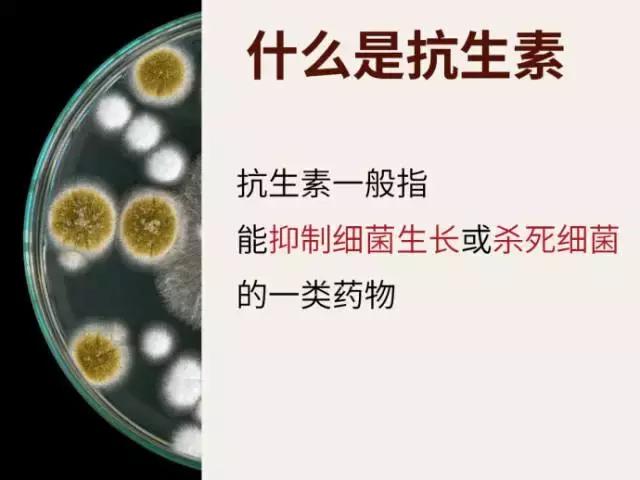

先来科普一下「抗生素」和「消炎药」的区别:

简单来说:

抗生素是用来抑制或杀死细菌的药物;